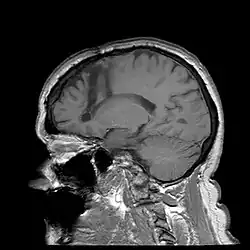

Lobotomie (ook wel: leukotomie) is een chirurgische operatie die rond het midden van de 20e eeuw werd toegepast. Tijdens de ingreep wordt de verbinding van het voorhoofdsgedeelte van de hersenen en de rest van de hersenen en het zenuwstelsel door een insnijding bijna geheel verbroken. De chirurg boorde eerst twee gaten in de schedel van de plaatselijk verdoofde patiënt en maakte de incisie in de hersenen. Later ontstond een snellere, 'transorbitale' methode zonder boren: een instrument werd onder plaatselijke verdoving boven de oogbol, onder het ooglid door, de schedel in gedreven en dan in de hersenen heen en weer bewogen.

De eerste systematische experimenten door de neuroloog António Egas Moniz en de chirurg Almeida Lima van de Universiteit van Lissabon dateren van 1935, waarbij de frontale cortex en de rest van de hersenen werd doorgesneden. De resultaten waren tamelijk goed, in het bijzonder bij de behandeling van ernstige depressie, hypochondrie, en angst- of dwangstoornissen, hoewel sterke persoonlijkheidsveranderingen optraden en 4 procent van de patiënten de operatie niet overleefde.[5] Ondanks deze risico's werd de methode vooral in de VS met enthousiasme begroet als behandelwijze voor anders onbehandelbare aandoeningen. Rond 1937 hadden Moniz en de zijnen zo'n 40 lobotomieën uitgevoerd en werd het een beroepsstandaard. Moniz kreeg in 1949 zelfs een Nobelprijs.[6] Zijn methode wordt doorgaans 'lobotomie' genoemd, hoewel dit eigenlijk een term is voor een breder scala aan chirurgische procedures.

Lobotomie werd in de Verenigde Staten op grotere schaal toegepast met gebruik van een nieuwe techniek die ontwikkeld was door Walter Freeman. Hij bedacht de transorbitale lobotomie, een methode zonder schedelboring. De patiënt werd eerst met een elektroshock bewusteloos gemaakt, vervolgens werd een ijspriem via een oogkas zeven centimeter diep de hersenen in geslagen.[7][8] Vanaf 1945 tot 1960 prees hij orbitale lobotomie aan als effectieve behandelmethode. De nieuwe, relatief eenvoudige ingreep duurde nog maar een paar minuten en kon overal, ook buiten een operatiekamer, worden uitgevoerd. Hierdoor werd de lobotomie enige tijd gezien als een algemeen bruikbare behandelmethode voor allerlei problemen, zoals zelfs wangedrag van kinderen. Uiteindelijk hebben in de VS ca. 40.000, in het Verenigd Koninkrijk ca. 17.000 en in Scandinavië ca. 9300 mensen deze specifieke operatie ondergaan, zonder dat er serieus wetenschappelijk onderzoek naar de effectiviteit van de methode was gedaan.